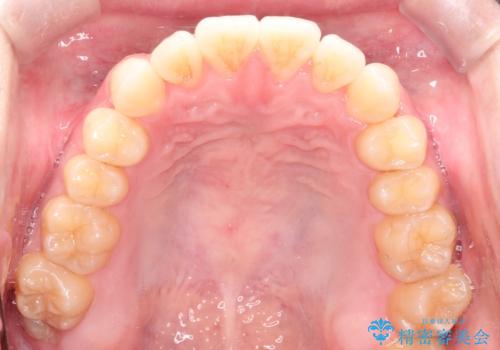

前歯のデコボコ インビザラインによる目立たない矯正

- 前歯のデコボコを主訴に来院された患者様です。

目立たないそうちをご希望されたので、インビザラインにて治療することとしました。

歯と歯の間をわずかに削ってスペースをつくり、デコボコを改善しました。